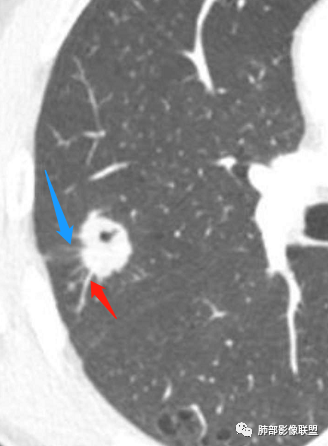

右肺上叶后段占位病灶,病灶不规则,周围胸膜线性牵拉,病灶部分周围有晕,病灶内见不规则空洞,未见明显引流支气管,长毛刺,多分叶、肿块边缘部分L型,可见血管直接供养。增强见点状坏死、病灶内血管。综上考虑恶性可能性大,鉴别隐球菌。

右肺上叶结节,浅分叶膨隆,边缘可见胸膜牵拉及血管集束,不规则厚壁空洞,不均匀强化,血管进入病灶,边缘毛燥,考虑低分化腺癌,鉴别隐球菌。

右肺结节,分叶、长短毛刺,边缘略膨隆,胸膜牵拉,血管进入病灶,收缩力较弱,有血管聚集征,洞壁尚规整,低强化,坏死边缘规整。考虑炎性,隐球,鉴别腺癌。

晨读,右肺上叶结节,边缘膨隆、分叶,部分边缘有平直,可见多发毛刺及胸膜牵拉,牵拉线清秀,收缩力弱,内密度不均,可见片状低密度影及空洞,增强后不均匀强化,血管集束,考虑良性,肉芽肿性结节,鉴别腺癌

晨读:双肺胸膜下多发小气囊,大小不一,右肺结节,内部可见小空洞,洞壁光滑,厚薄不一,偏心性生长,近段血管束增粗,有分叶,毛刺(软),有晕征,平扫密度尚可,增强后不均匀强化,可见低密度坏死,及部分血管穿行,体检发现,考虑恶性:腺癌,鉴别炎性结节

右肺上叶结节,周围毛刺明显,其内有小炮征,分叶,强化中度,其内可见坏死,支气管有截断,考虑腺癌,鳞癌待排。病灶的上缘有一个小支气管进入,然后截断了

晨读:男,67岁,体检发现右肺结节。近圆形,支气管及伴行血管进入结节,进入结节后支气管堵塞,血管走形尚自然,结节内血管边缘凹凸不平。远端边缘见毛刺(软毛刺?)及分叶。见胸膜牵拉。实变中见空洞。整体膨胀感不明显。考虑炎性肉芽肿可能,隐球菌病可能性大。注意鉴别鳞癌、结核。